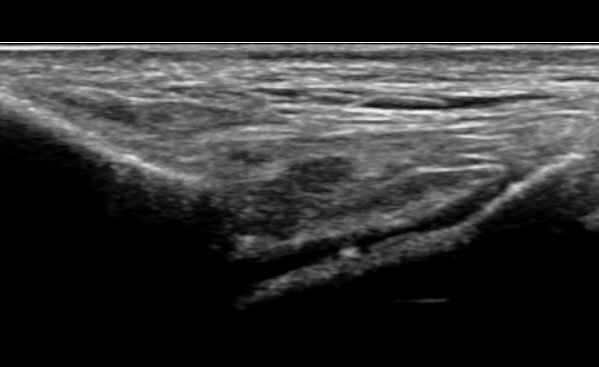

ÃÊÀ½ÆÄ À¯µµÇÏ Áֻ縦 À§Çؼ´Â ¸ÕÀú ¹ß¸ñÀÇ È¾´Ü¸é°Ë»ç¸¦ ½ÃÇàÇÏ¿© ¹ßµî µ¿¸Æ°ú ½ÉºÎºñ°ñ½Å°æÀÇ À§Ä¡¸¦ ÆÄ¾ÇÇÑ´Ù. ¹ßµîµ¿¸ÆÀº ´ë°³ À幫Áö½ÅÀü°Ç°ú ÀåÁ·½ÅÀü°Ç »çÀÌ¿¡ À§Ä¡ÇÏ°í ½ÉºÎºñ°ñ½Å°æÀº ¹ßµîµ¿¸ÆÀÇ ³»Ãø ¶Ç´Â À§Ä¡¿¡ µû¶ó ¿ÜÃø¿¡ À§Ä¡ÇÑ´Ù(»çÁø 1). ¹ßµîµ¿¸ÆÀÌ À幫Áö½ÅÀü°Ç°ú ÀåÁ·½ÅÀü°Ç »çÀÌ¿¡ Á¸ÀçÇÏ´Â °ÍÀ» È®ÀÎ ÈÄ Àü°æ°ñ°Ç¿¡ À§Ä¡½Ã۸é Àü°æ°ñ°ÇÀ» âÀ¸·Î ¹ß¸ñ°üÀý°À» È®ÀÎÇÒ ¼ö ÀÖ´Ù(»çÁø 2). Àü°æ°ñ°Ç ³»Ãø¿¡¼ Áֻ縦 ¿øÇϸé ŽÃËÀÚ¸¦ ¾à°£ ³»ÃøÀ¸·Î ±â¿ïÀÌ¸é ³»ÃøÀÇ ¹ß¸ñ°üÀýÀ» °üÂûÇÒ ¼ö ÀÖ´Ù (»çÁø 3).

ÁÖ»ç¹Ù´ÃÀº ŽÃËÀÚÀÇ ¾à°£ ¿ÜÃø(5 mm)¿¡¼ °üÀý°ÀÇ ±íÀ̸¦ °¨¾ÈÇÏ¿© ÁÖ»ç¹Ù´ÃÀÇ ³¡ÀÌ Å½ÃËÀÚ Æø(µÎ²²)À» ³Ñ¾î°¡Áö ¾Êµµ·Ï °¢µµ¸¦ ÁÖ¾î »ðÀÔÇÏ¿© ¹Ù´Ã ³¡ÀÌ °üÀý°³»¿¡ À§Ä¡ÇÑ °ÍÀ» È®ÀÎ ÈÄ ¾à°£ÀÇ ÁÖ»ç¾×À» ÁÖ»ç ÈÄ ÁÖ»ç¾×ÀÌ °üÀý³»·Î Àß µé¾î°¡°í ½ÉÇÑ ÅëÁõ µî ¹®Á¦°¡ ¾øÀ¸¸é ³ª¸ÓÁö ÁÖ»ç¾×À» ÁÖ»çÇÑ´Ù. ÁÖ»ç¹Ù´ÃÀÌ °üÀý³»¿¡ À§Ä¡Çϰí ÀÖÁö¸¸ ÁÖ»ç¾×ÀÌ Àß ¾Èµé¾î°¡´Â °æ¿ì´Â ÁÖ»ç¹Ù´ÃÀÌ ¿¬°ñ¿¡ °úµµÇÏ°Ô Á¢ÃËÇÑ °æ¿ì À̹ǷΠ¹Ù´ÃÀ» ¾à°£ »« ÈÄ ÁÖ»çÇÑ´Ù. ÁÖ»ç ÃÊÀ½ÆÄ µ¿¿µ»ó ÷ºÎ µ¿¿µ»ó 1(¿ÜÃø) ÷ºÎ µ¿¿µ»ó 2(³»Ãø) Âü°í  |